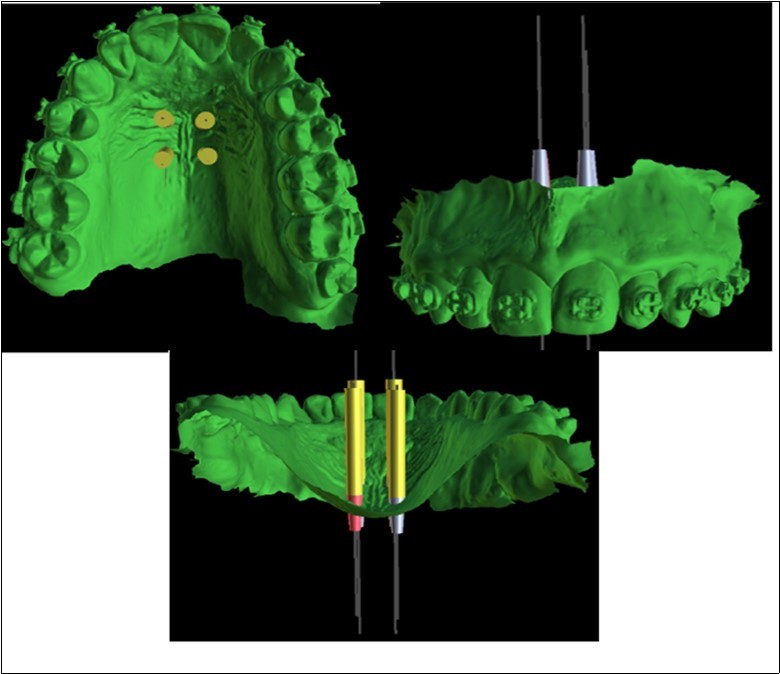

The precise position and angulation of the mini-implants is replicated by 4 cylindrical metallic guides taking into consideration the following parameters: bone thickness, soft tissue thickness and anatomical surrounding structures. The most appropriate site for the placement of mini-implants is: 3 mm lateral to the suture in the first premolar region. (Figure 3,Figure 4)

Figure 3.Positioning of the 4 mini-implants, visualized on the basis of the intraoral scan